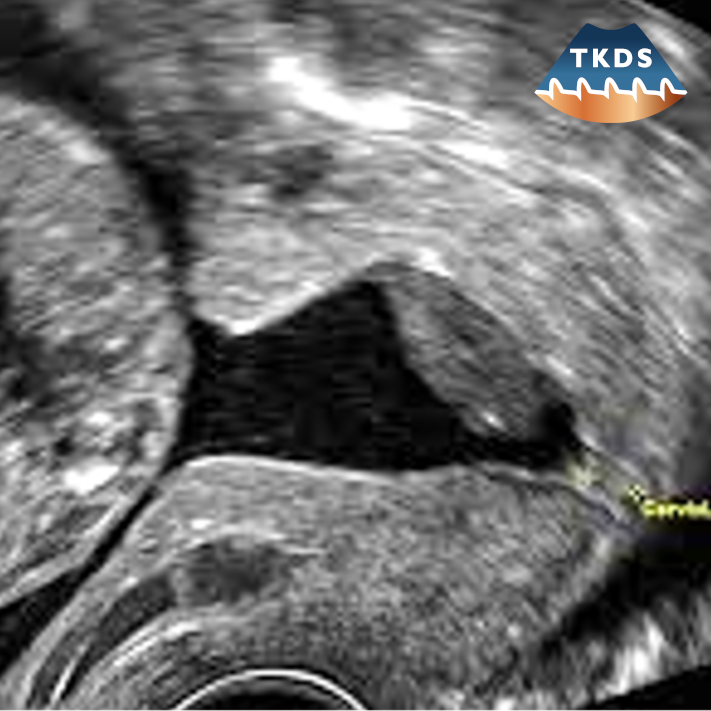

Die Dopplersonografie ist eine wertvolle additive Methode in der geburtshilflichen Ultraschalluntersuchung, der Sonografie des weiblichen Beckens und der Mammasonografie.

Da alle dopplersonografischen Themen immer auch grundsätzliche Fragen geburtshilflicher Diagnostik und geburtshilflichen Managements berühren, bieten unsere Kursreihen gleichzeitig ein Update der modernen Pränataldiagnostik und Geburtsmedizin.